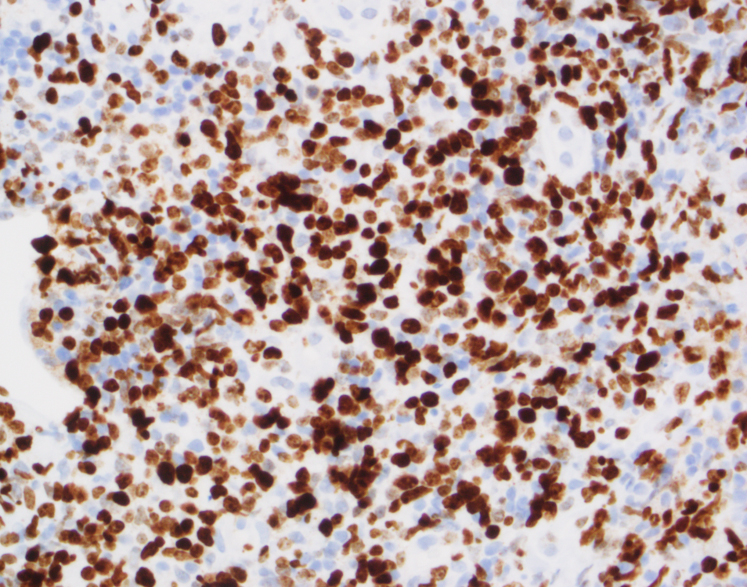

By immunohistochemistry, CD3 highlights the lymphoma cells, which comprise the majority of the lymphoid infiltrate. The lymphoma cells co-express CD56 and CD7 (dim) and are negative for CD2 and CD5. The lymphoma cells also express cytotoxic markers perforin and granzyme (major subset). CD20 highlights only rare small clusters of B-cells. The lymphoma cells are also positive for EBER (Epstein-Barr Virus encoded RNA) in situ hybridization. The Ki67 (MIB1) proliferation index is 60% with focal areas exhibiting up to 80%.